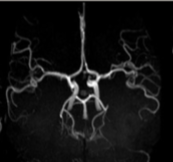

What type of view are we observing the COW at?

axial

coronal

sagittal